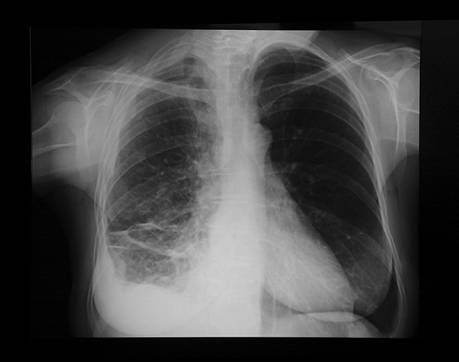

hôtel jusqu'à sa retraite. A l'examen, la patiente est apyrétique. Elle a perdu

5 kg au cours des deux derniers mois. L'auscultation trouve une abolition du

murmure vésiculaire à la base droite. Le reste de l'examen est normal. Une

radiographie thoracique est effectuée.

Décrivez

les anomalies et interprétez la radiographie thoracique.